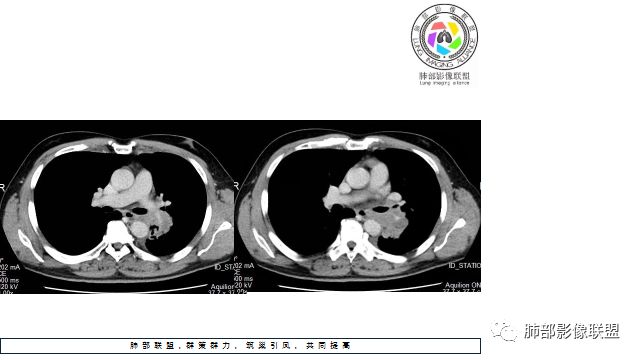

1.左下肺门区巨大肿块,支气管显示不清,轻度阻塞性炎症,没有明显肺不张,提示管腔受压狭窄可能性大于堵塞,这较少见于鳞癌。

2.病灶边缘光滑,未见明显分叶、毛刺,未见明显强化,这符合腺癌影像学特点,却符合神经内分泌癌表现。

3.病灶内密度均匀,轻到中度均匀强化,大病灶未见明显液化坏死区及空洞,不符合鳞癌而符合小细胞肺癌特点。

4.病灶内有肺动脉走形,血管局部受压,未见破坏,病灶乏血供,呈血管包埋或血管造影征;侵袭性力强及破坏力弱、血管漂浮都符合SCLC,所以鳞癌的可能性也不大。

5.左肺门块影或淋巴结肿大,竭力挤兑肺门血管结构,呈冰冻肺门;有时候SCLC可以单独呈现冰冻肺门,而没有没有冰冻纵隔。